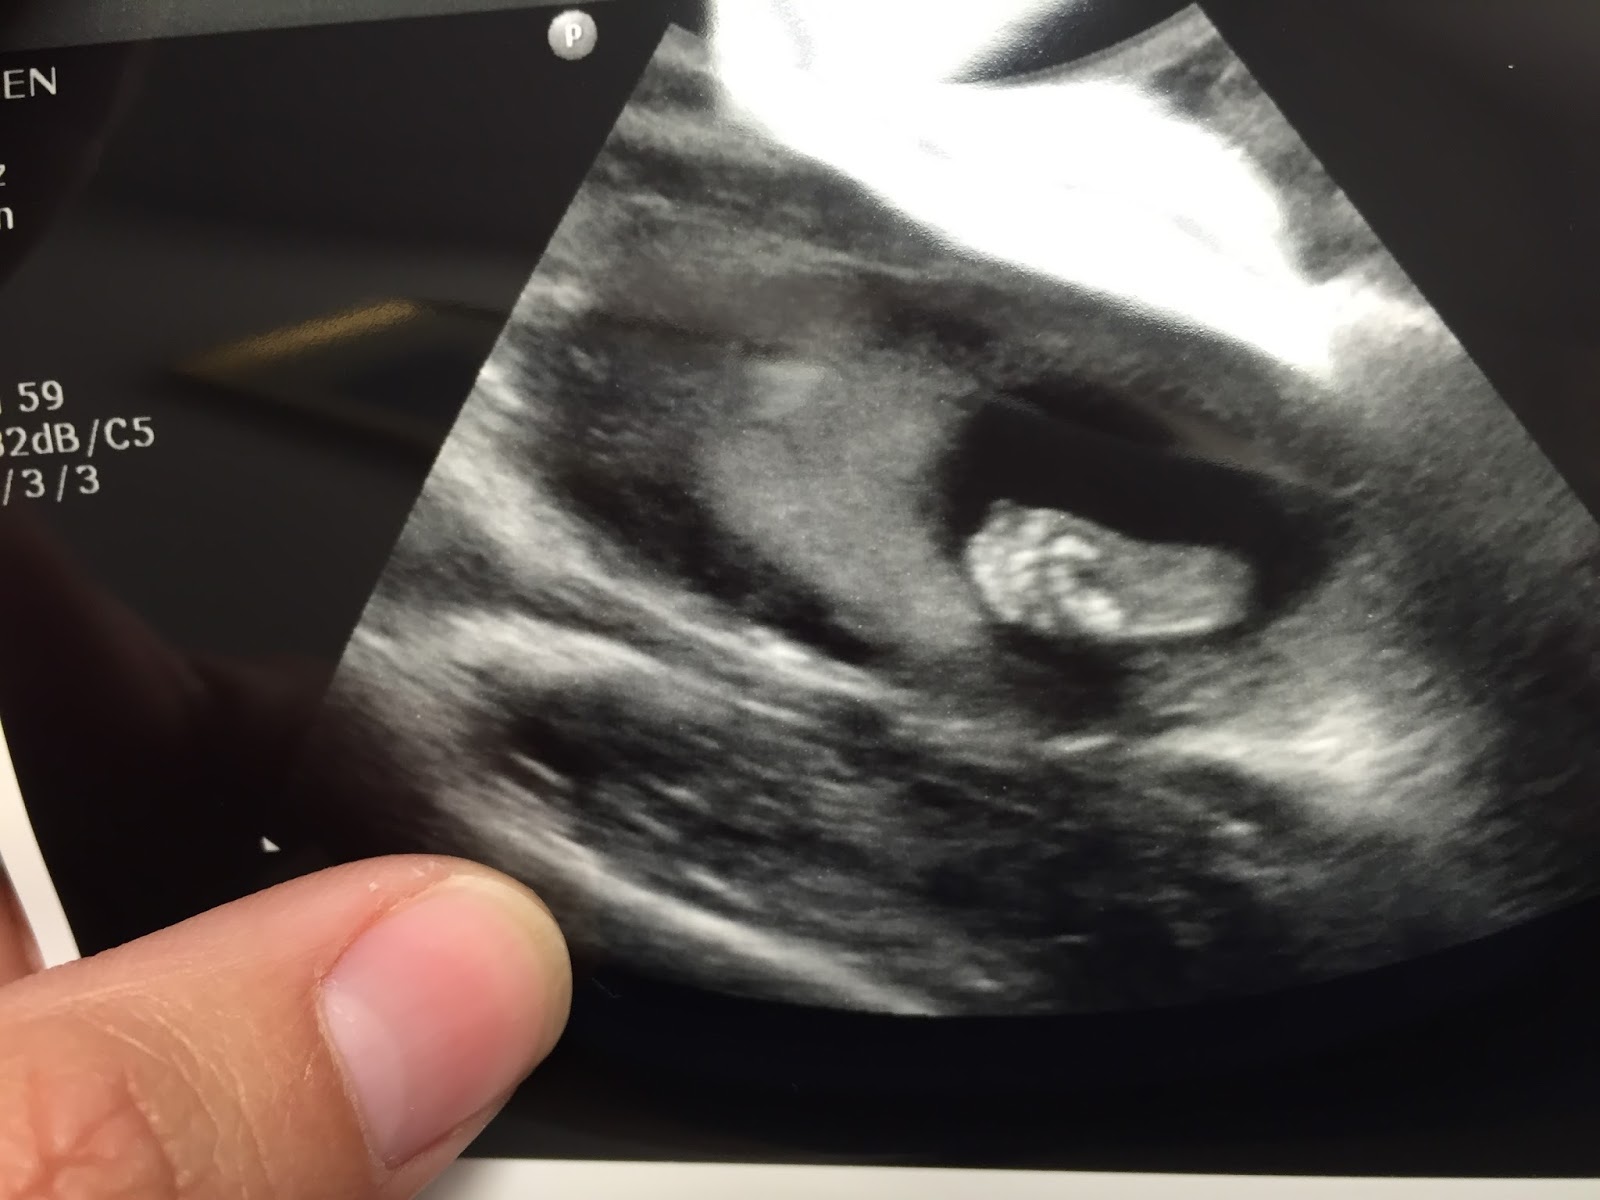

--I'm also in love with this tiny foot, which I got to see at another ultrasound we had a week and a half ago... <3